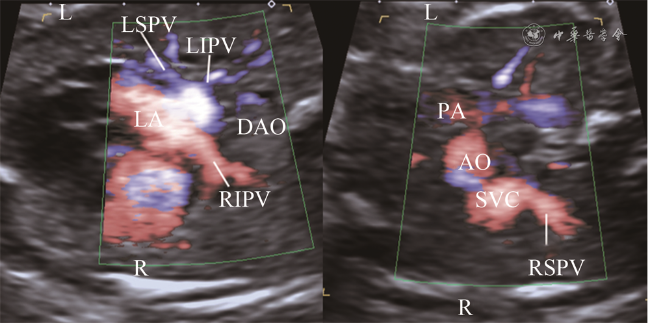

图2 胎儿心上型完全型肺静脉异位引流超声图像。右图胸部横切面彩色血流显示左上肺静脉远端分支分布于左侧前部1/2肺野,左下肺静脉远端分支分布于左侧后部1/2肺野,右上肺静脉远端分支分布于右侧前部1/2肺野,右下肺静脉远端分支分布于右侧后部1/2肺野(对应动态图2),4条肺静脉近心端均未回流入左心房,呈现左心房后方汇聚征,肺静脉分支间距减小;左图为二维超声对比图像

动态图2 胎儿心上型完全型肺静脉异位引流超声动态图像

追踪36例TAPVD胎儿肺组织4大区域回流显示4条肺静脉均未汇入左心房,34例肺静脉近心端呈现左心房后方汇聚征(图2动态图2),包括心上型25例,心内型7例,心下型2例。心上型TAPVD胎儿,其中20例4条肺静脉于左心房后方汇聚成肺总静脉腔,然后向头侧走行,最终汇入上腔静脉;3例胎儿显示3条肺静脉引流3大区域,于左心房后方汇聚成肺总静脉腔,肺总静脉腔向头侧走行过程中收集剩余区域肺静脉1条共同入上腔静脉。心内型TAPVD胎儿7例,其中6例4条肺静脉于左心房后下部汇聚成肺总静脉腔回流入冠状静脉窦,1例4条肺静脉于左心房后方汇聚成肺总静脉腔,直接回流入右心房。心下型TAPVD胎儿2例,4条肺静脉均于左心房后方汇聚成肺总静脉腔,然后向足侧走行汇入门静脉窦。混合型TAPVD 2例,1例左侧上肺及下肺静脉汇合后向头侧走行汇入上腔静脉,右侧上肺及下肺静脉汇合后向足侧走行入下腔静脉;1例左侧上肺及下肺静脉汇合后向头侧走行入上腔静脉,右侧上肺及下肺静脉汇合后直接回流入右心房。

二、区域血流追踪法与APVD胎儿超声诊断

应用区域血流定位好肺静脉分支后,继续追踪其是否回流入左心房,用于鉴别正常与APVD胎儿。本研究中36例TAPVD胎儿呈现左心房后方汇聚征,而正常胎儿汇入左心房的声像图表现呈螃蟹征,如同4条“腿”插入左心房壁。二者区别在于正常胎儿4条肺静脉插入左心房壁之间,且分支间距较大,而TAPVD胎儿肺静脉向左心房后方共同肺静脉腔汇聚,分支间距较小,在彩色血流辨别不清时,需结合二维超声对比观察。本研究中3例TAPVD胎儿3条肺静脉汇入共同肺静脉腔,通过区域血流追踪发现剩余1条肺静脉在共同肺静脉腔移行为垂直静脉的过程中汇入,这也使得这3例胎儿最终诊断为TAPVD。对共同肺静脉腔的血流进一步追踪,可显示肺静脉向上、向下、向冠状静脉窦或直接向右心房回流,从而对TAPVD的分型做进一步的判断。